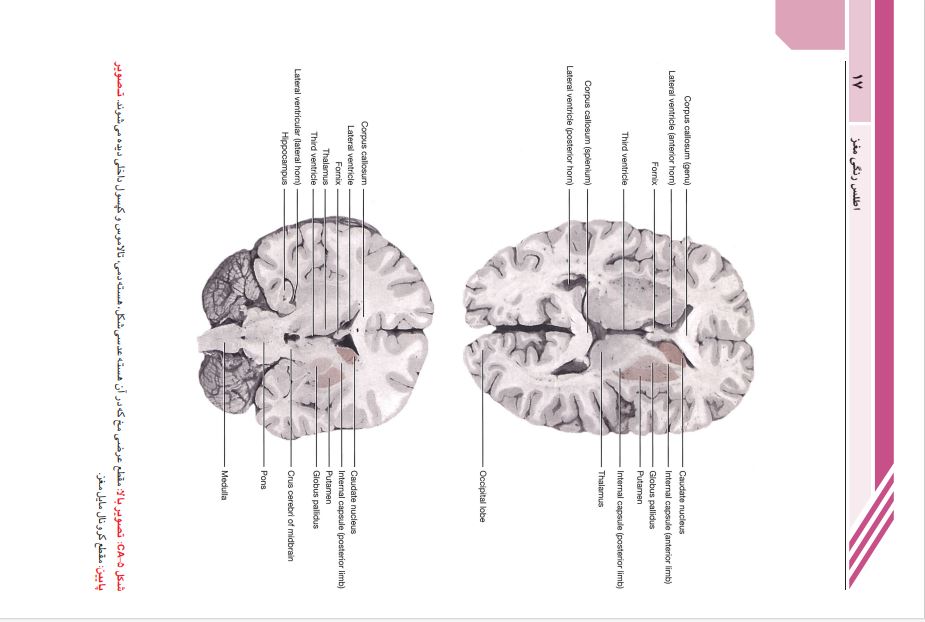

این کتاب ترجمه ی ویرایش نهم نوروآناتومی بالینی اسنل است.. این کتاب دربرگیرنده ی پایه ای ترین نکات علمی نوروآناتومی است که برای حرفه پزشکی ضروری است. در این ویرایش نویسنده ی کتاب تغییر یافته است. مطالب هر فصل مرور و ویرایش شده تا نکات نوروآناتومی به بهترین نحو ارائه شوند. تصاویر قبلی کتاب به روز شده و رنگ بندی آن ها تغییر یافته تا مطالب ارائه شده در هر تصویر گویاتر شوند.تصاویر MRI و میکروگراف های بافت شناسی با کیفیت بالا تهیه شده اند تا اطلاعات بصری دقیق تری ارائه دهند.

__فصل13:مخ